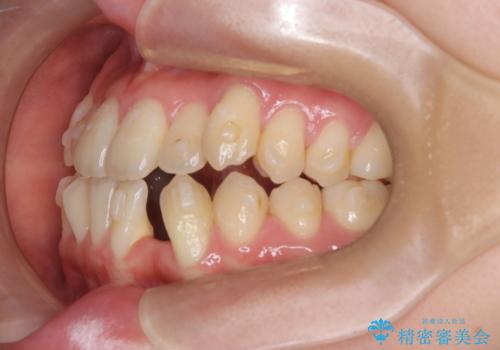

- 他院でインビザライン矯正を行っていたものの、通院先の閉院により治療が継続できなくなったとのことで来院されました。

診査の結果、すでに下顎前歯の抜歯が行われていましたが、マウスピースの適合が著しく悪くなっており、歯が計画通りに動いていない状態でした。また、歯を支える骨の厚みや歯肉の薄さを考慮すると、このままマウスピースによる傾斜移動を続けるのは歯肉退縮(歯茎が下がること)のリスクが非常に高いと判断。